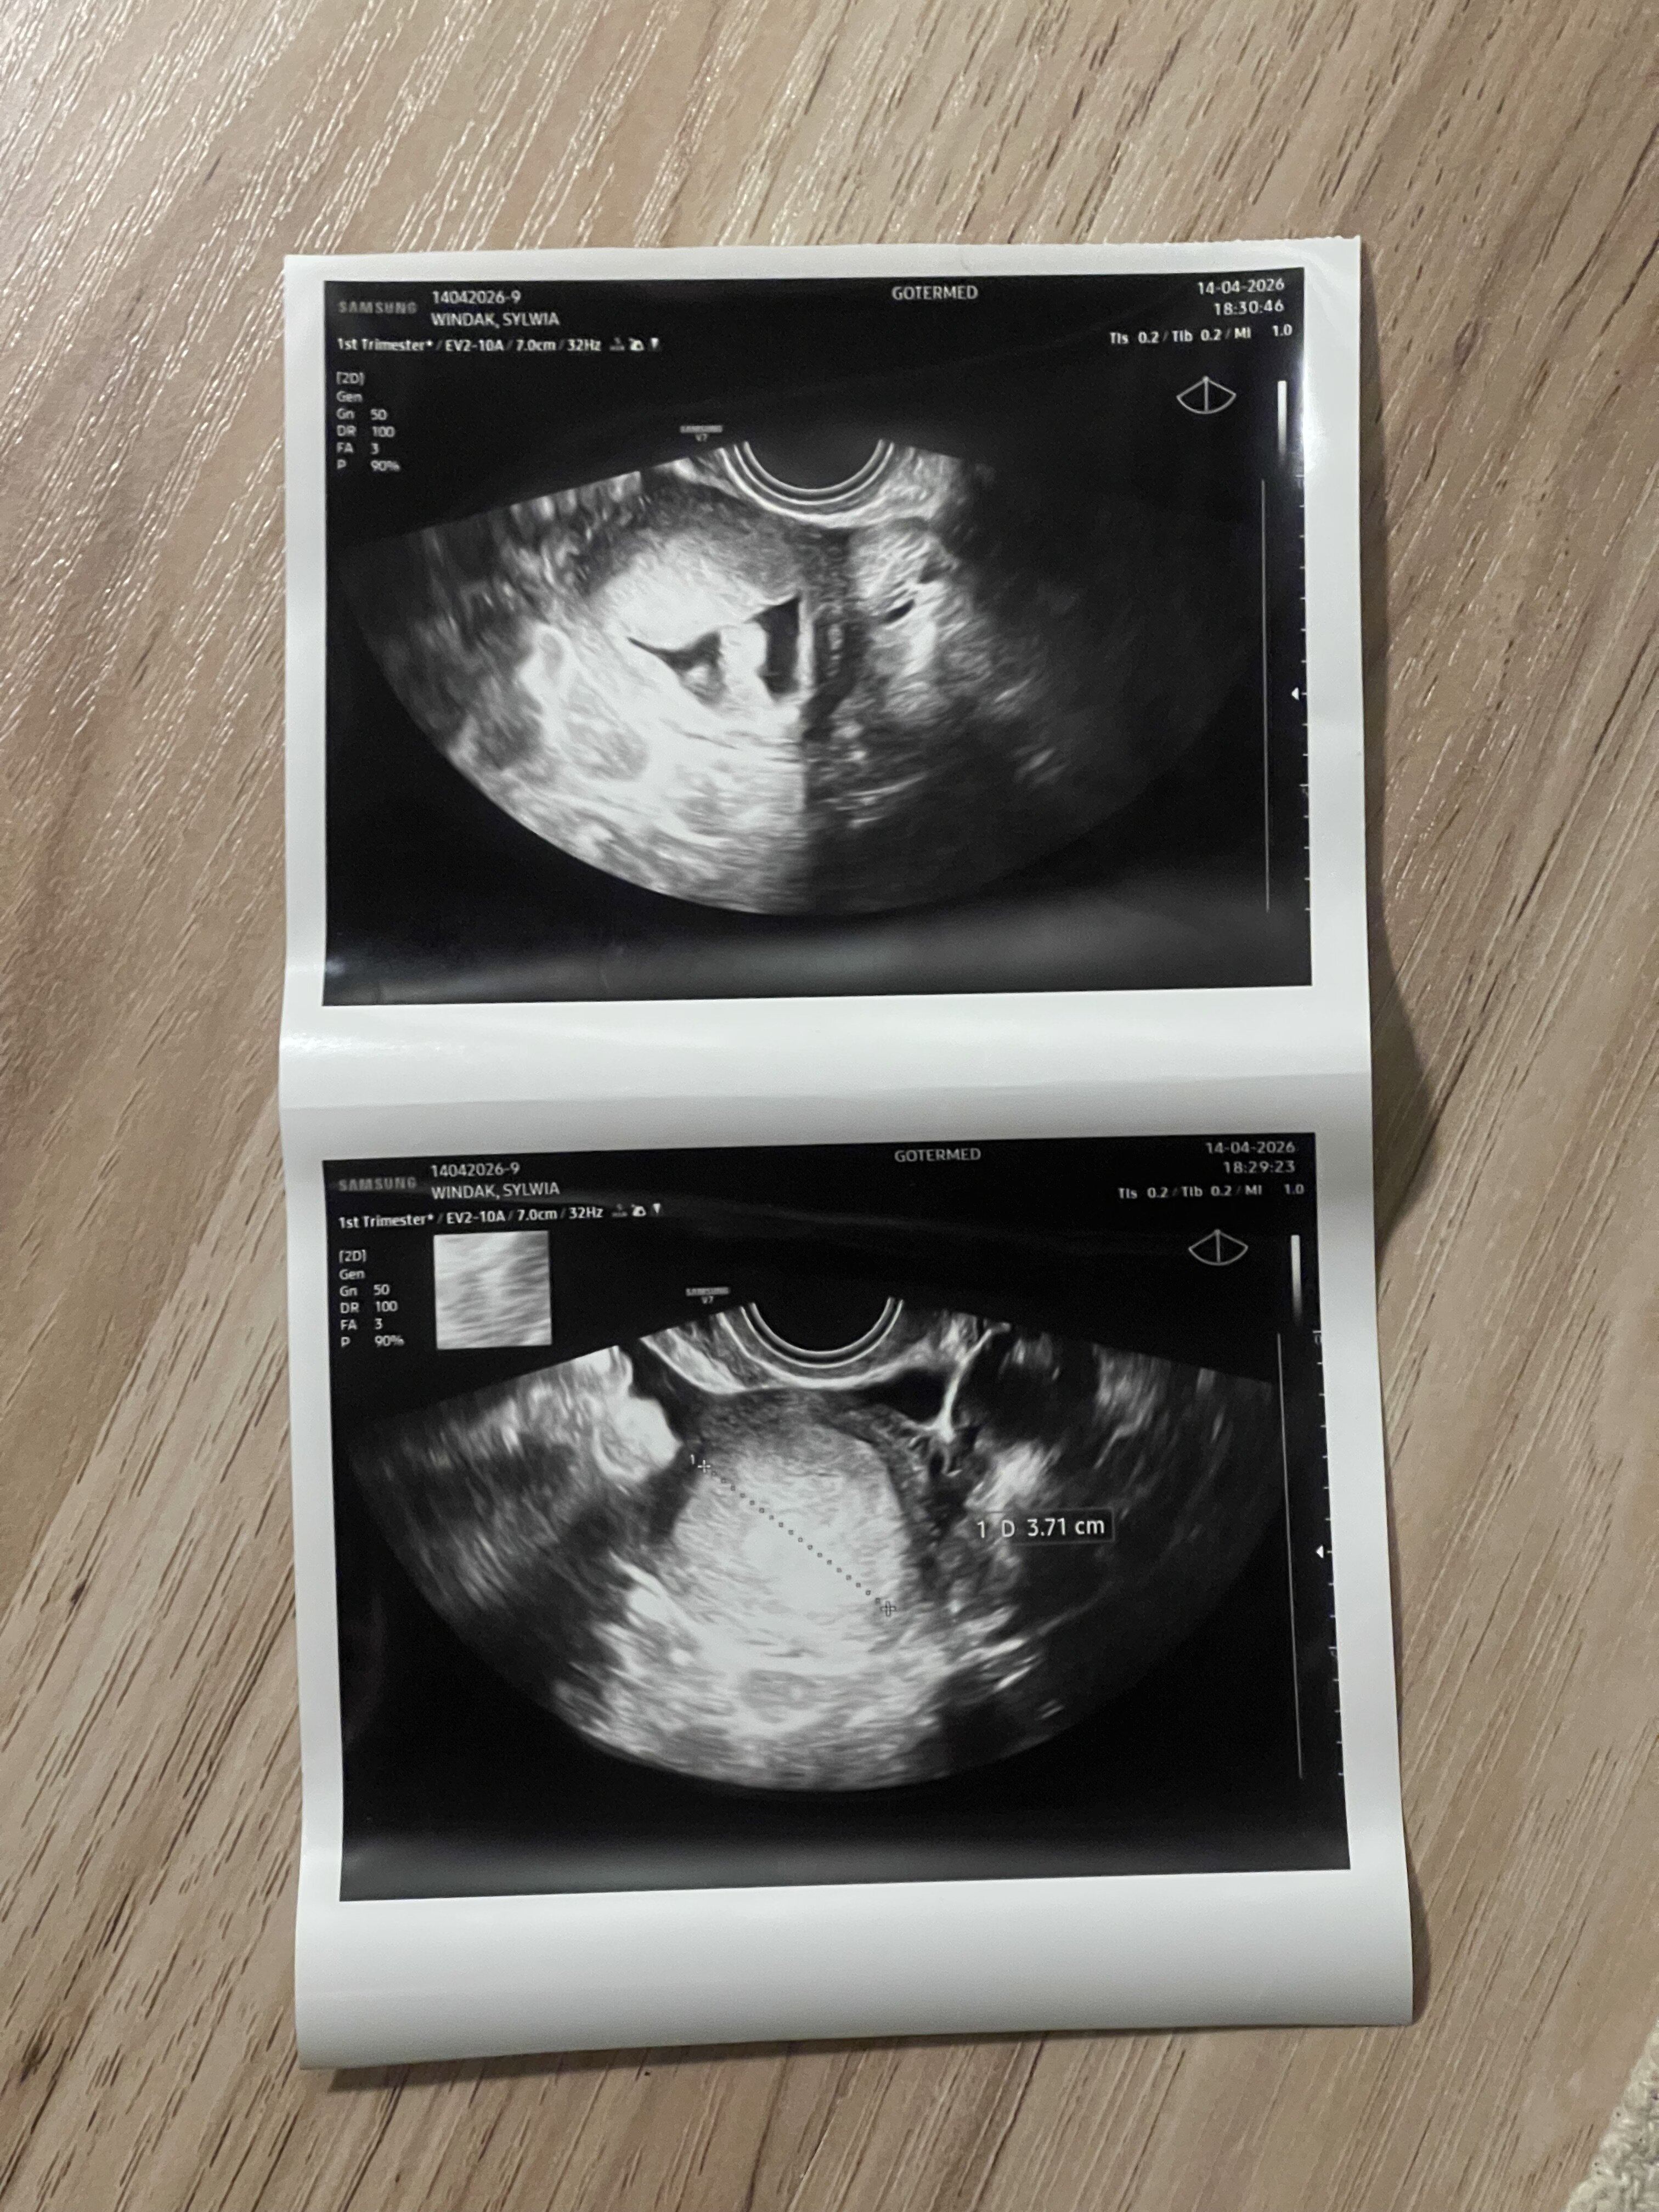

Hej dziewczyny, dzisiaj byłam u ginekologa na USG. Jestem w 4 tygodniu ciąży. Beta 147. Podrzucam zdjęcie z USG. Czy któraś z was może mi powiedzieć co widać na pierwszym zdjęciu? Z całych tych emocji zapomniałam zapytać, ponieważ pani ginekolog powiedziała że endometrium nie wygląda prawidłowo, jest bardzo duże. Dziękuję i pozdrawiam

• IMG_4212.jpeg

1,6 MB · Wyświetleń: 152

Na zdj z USG które dołączyłam w pierwszym poście jest długość 3,7cm.